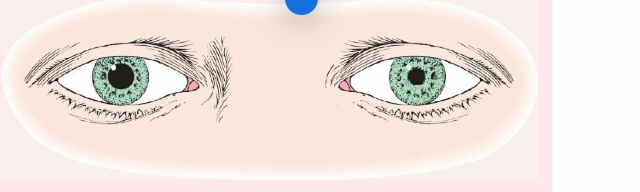

exophthalmos

protruding eyeballs and retracted eyelids